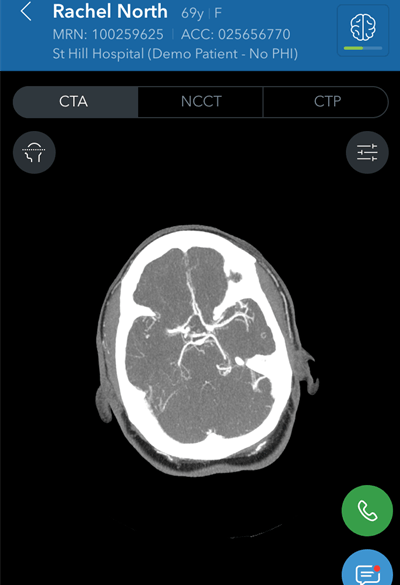

In stroke care, time is brain. The winner of the Best New Radiology Software award -- Viz LVO from software developer Viz.ai -- is designed to speed up diagnosis and treatment by serving as an early-warning system. The software analyzes CT angiography (CTA) images after acquisition and immediately notifies providers that a patient may be having a stroke.

If the artificial intelligence-based software detects a suspected large vessel occlusion (LVO) stroke on a CTA exam, it triggers a mobile app push notification/alarm for the institution's stroke specialist team, which typically includes a neuroradiologist, an interventional radiologist, and the neurologist on call. The median time from image acquisition to notification is less than six minutes, according to the company. The physicians can then click on the notification on a mobile device and view nondiagnostic images using a mobile DICOM viewer. With Viz.ai's companion Viz CTP software, they can also obtain blood flow measurements in the affected area of the brain.